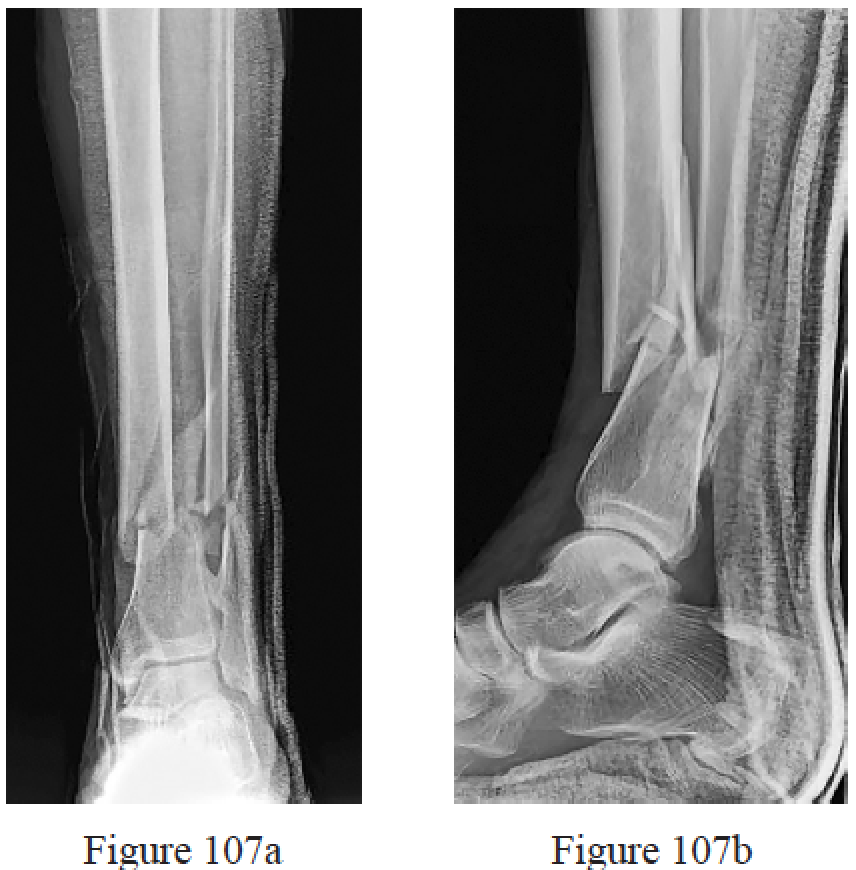

Ovaska MT, Madanat R, Mäkinen TJ. Predictors of Postoperative Wound Necrosis Following Primary Wound Closure of Open Ankle Fractures. Foot Ankle Int. 2016 Apr;37(4):401-6. doi: 10.1177/1071100715609182. PubMed PMID: 26830839.

Jenkinson RJ, Kiss A, Johnson S, Stephen DJ, Kreder HJ. Delayed wound closure increases deep-infection rate associated with lower-grade open fractures: a propensity-matched cohort study. J Bone Joint Surg Am. 2014 Mar 5;96(5):380-6. doi: 10.2106/JBJS.L.00545. PubMed PMID: 24599199.